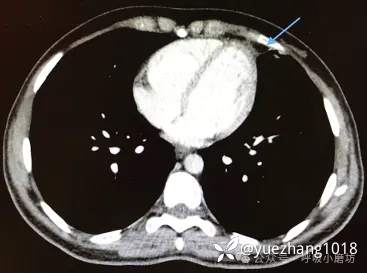

50岁男性患者,因“急性左胸痛3天”入院,疼痛随呼吸和体位改变加剧。

胸片见左心旁模糊影(图3A)。CT检查发现一边界清晰的脂肪性肿块,其内部可见致密条索影(图3B)。

图3A 胸部X线片显示左心旁高密度影(箭头所示);3B CT平扫显示被包裹的脂肪病灶,内部可见条索状影(箭头所示)

因不能完全排除脂肪肉瘤,患者接受了胸腔镜手术。

术后病理证实为“脂肪组织坏死伴炎细胞浸润”,未见肿瘤细胞。